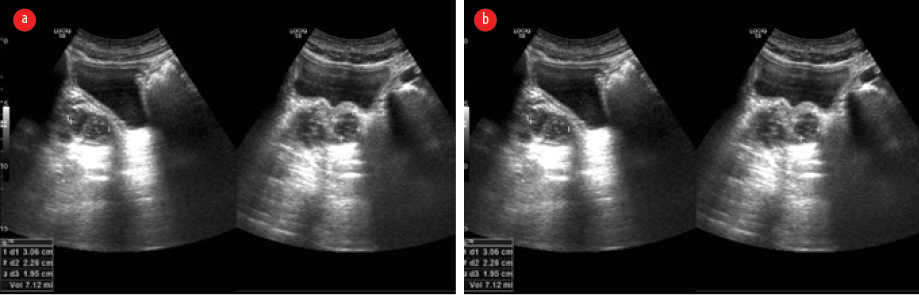

Ultrasonography of the abdomen revealed hepatosplenomegaly, prostatomegaly with abscess formation, and multiple splenic microabscesses [Figure 2]. The culture of his right knee aspirate yielded B. pseudomallei, but the blood culture was negative for the pathogen.

Figure 2: Ultrasonographic images of the abdomen. (a) Hepatosplenomegaly, prostatomegaly with abscess formation. (b) Multiple splenic microabscesses are seen.